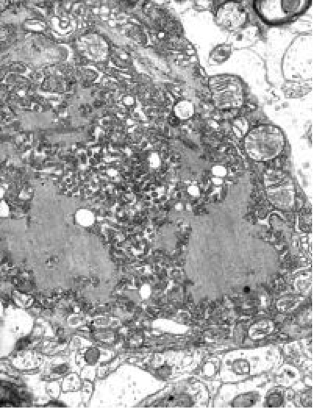

<狂犬病ウイルス (Rabies virus)>